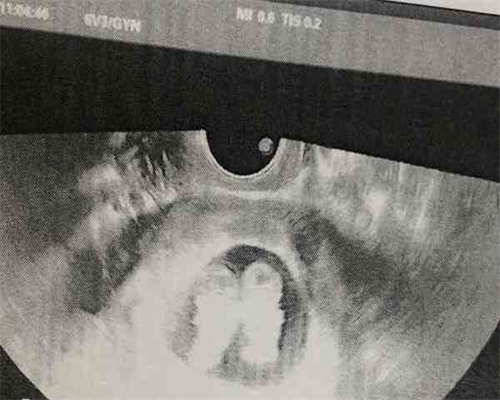

子宫子宫内膜异位症是一种难以治疗的疾病。它影响正常妊娠,因此是试管婴儿的适应症之一。子宫内膜异位症患者的试管婴儿成功率低于单纯输卵管因素(如输卵管不孕)患者的试管婴儿成功率。这种情况下,我们一方面要积极治疗子宫子宫内膜异位症,另一方面要做好试管婴儿的准备。